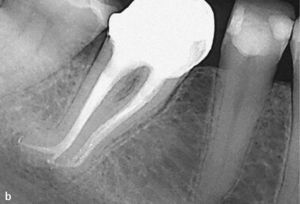

Antes de tomar una decisión sobre la conveniencia de instaurar un retratamiento endodóntico hay que asegurarse de que el diente se pueda conservar. En caso de le-siones de caries profunda que requieren probablemente un alargamiento coronario quirúrgico por medio de una osteotomía y una preparación subgingival, se ha de eva-luar con una actitud especialmente crítica los intentos repetidos de conservar el diente (figs. 2a y 2b). Además de los desafíos técnicos existentes a la hora de solventar los problemas que presentan los conductos, en el proce-so de toma de decisiones previo al inicio del tratamiento también hay que tener en cuenta la carga funcional pre-vista del diente. Especialmente en el caso de los dientes unirradiculares es necesario disponer de una porción de corona natural de al menos 2mm para la restauración38.

Radiografía inicial del diente 16 obtenida para deter-minar las perspectivas de conser-vación. No se visualiza bien la tra-yectoria del conducto radicular. Una infraobturación y una lesión de caries profunda distal sugieren que la inversión para conservar el diente será cuantiosa (a). Una vez finalizado el tratamiento endodóntico hará falta un alargamiento coronario quirúrgico o una extrusión ortodóncica para poder realizar una restauración con corona adecuada (b).